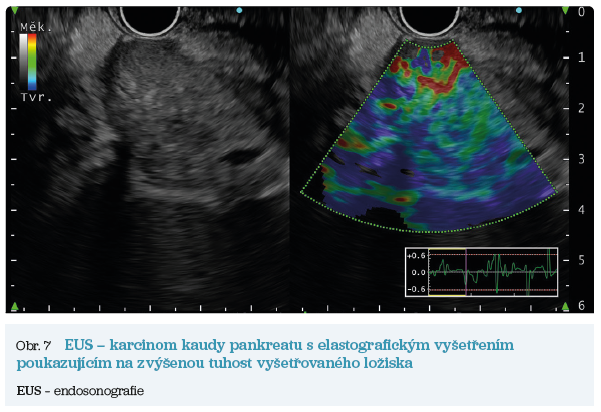

EUS umožňuje přesné vyšetření pankreatu. Lze také identifikovat a vyšetřit regionální lymfatické uzliny a vztah pankreatických lézí k okolním cévním strukturám. EUS může také sloužit jako navigace k odběru bioptického materiálu k cytologickému a histologickému vyšetření.21 AI je zde využívána k potvrzení malignity v IPMN. Kuwahara a kol. dosáhli s využitím 3 970 snímků a CNN algoritmu velké úspěšnosti v diferenciaci benigní a maligní IPMN s AUC 0,98.22 Řada studií se již zabývala AI asistovaným rozlišením chronické pankreatitidy a karcinomu pankreatu s AUC 0,940–0,986.23,24 Velká studie obsahující 1 174 461 snímků z celkem 583 případů hodnotící rozlišení autoimunitní pankreatitidy, karcinomu pankreatu, chronické pankreatitidy a normálního pankreatu dosáhla pro karcinom pankreatu AUC 0,97625 (obr. 6–9).